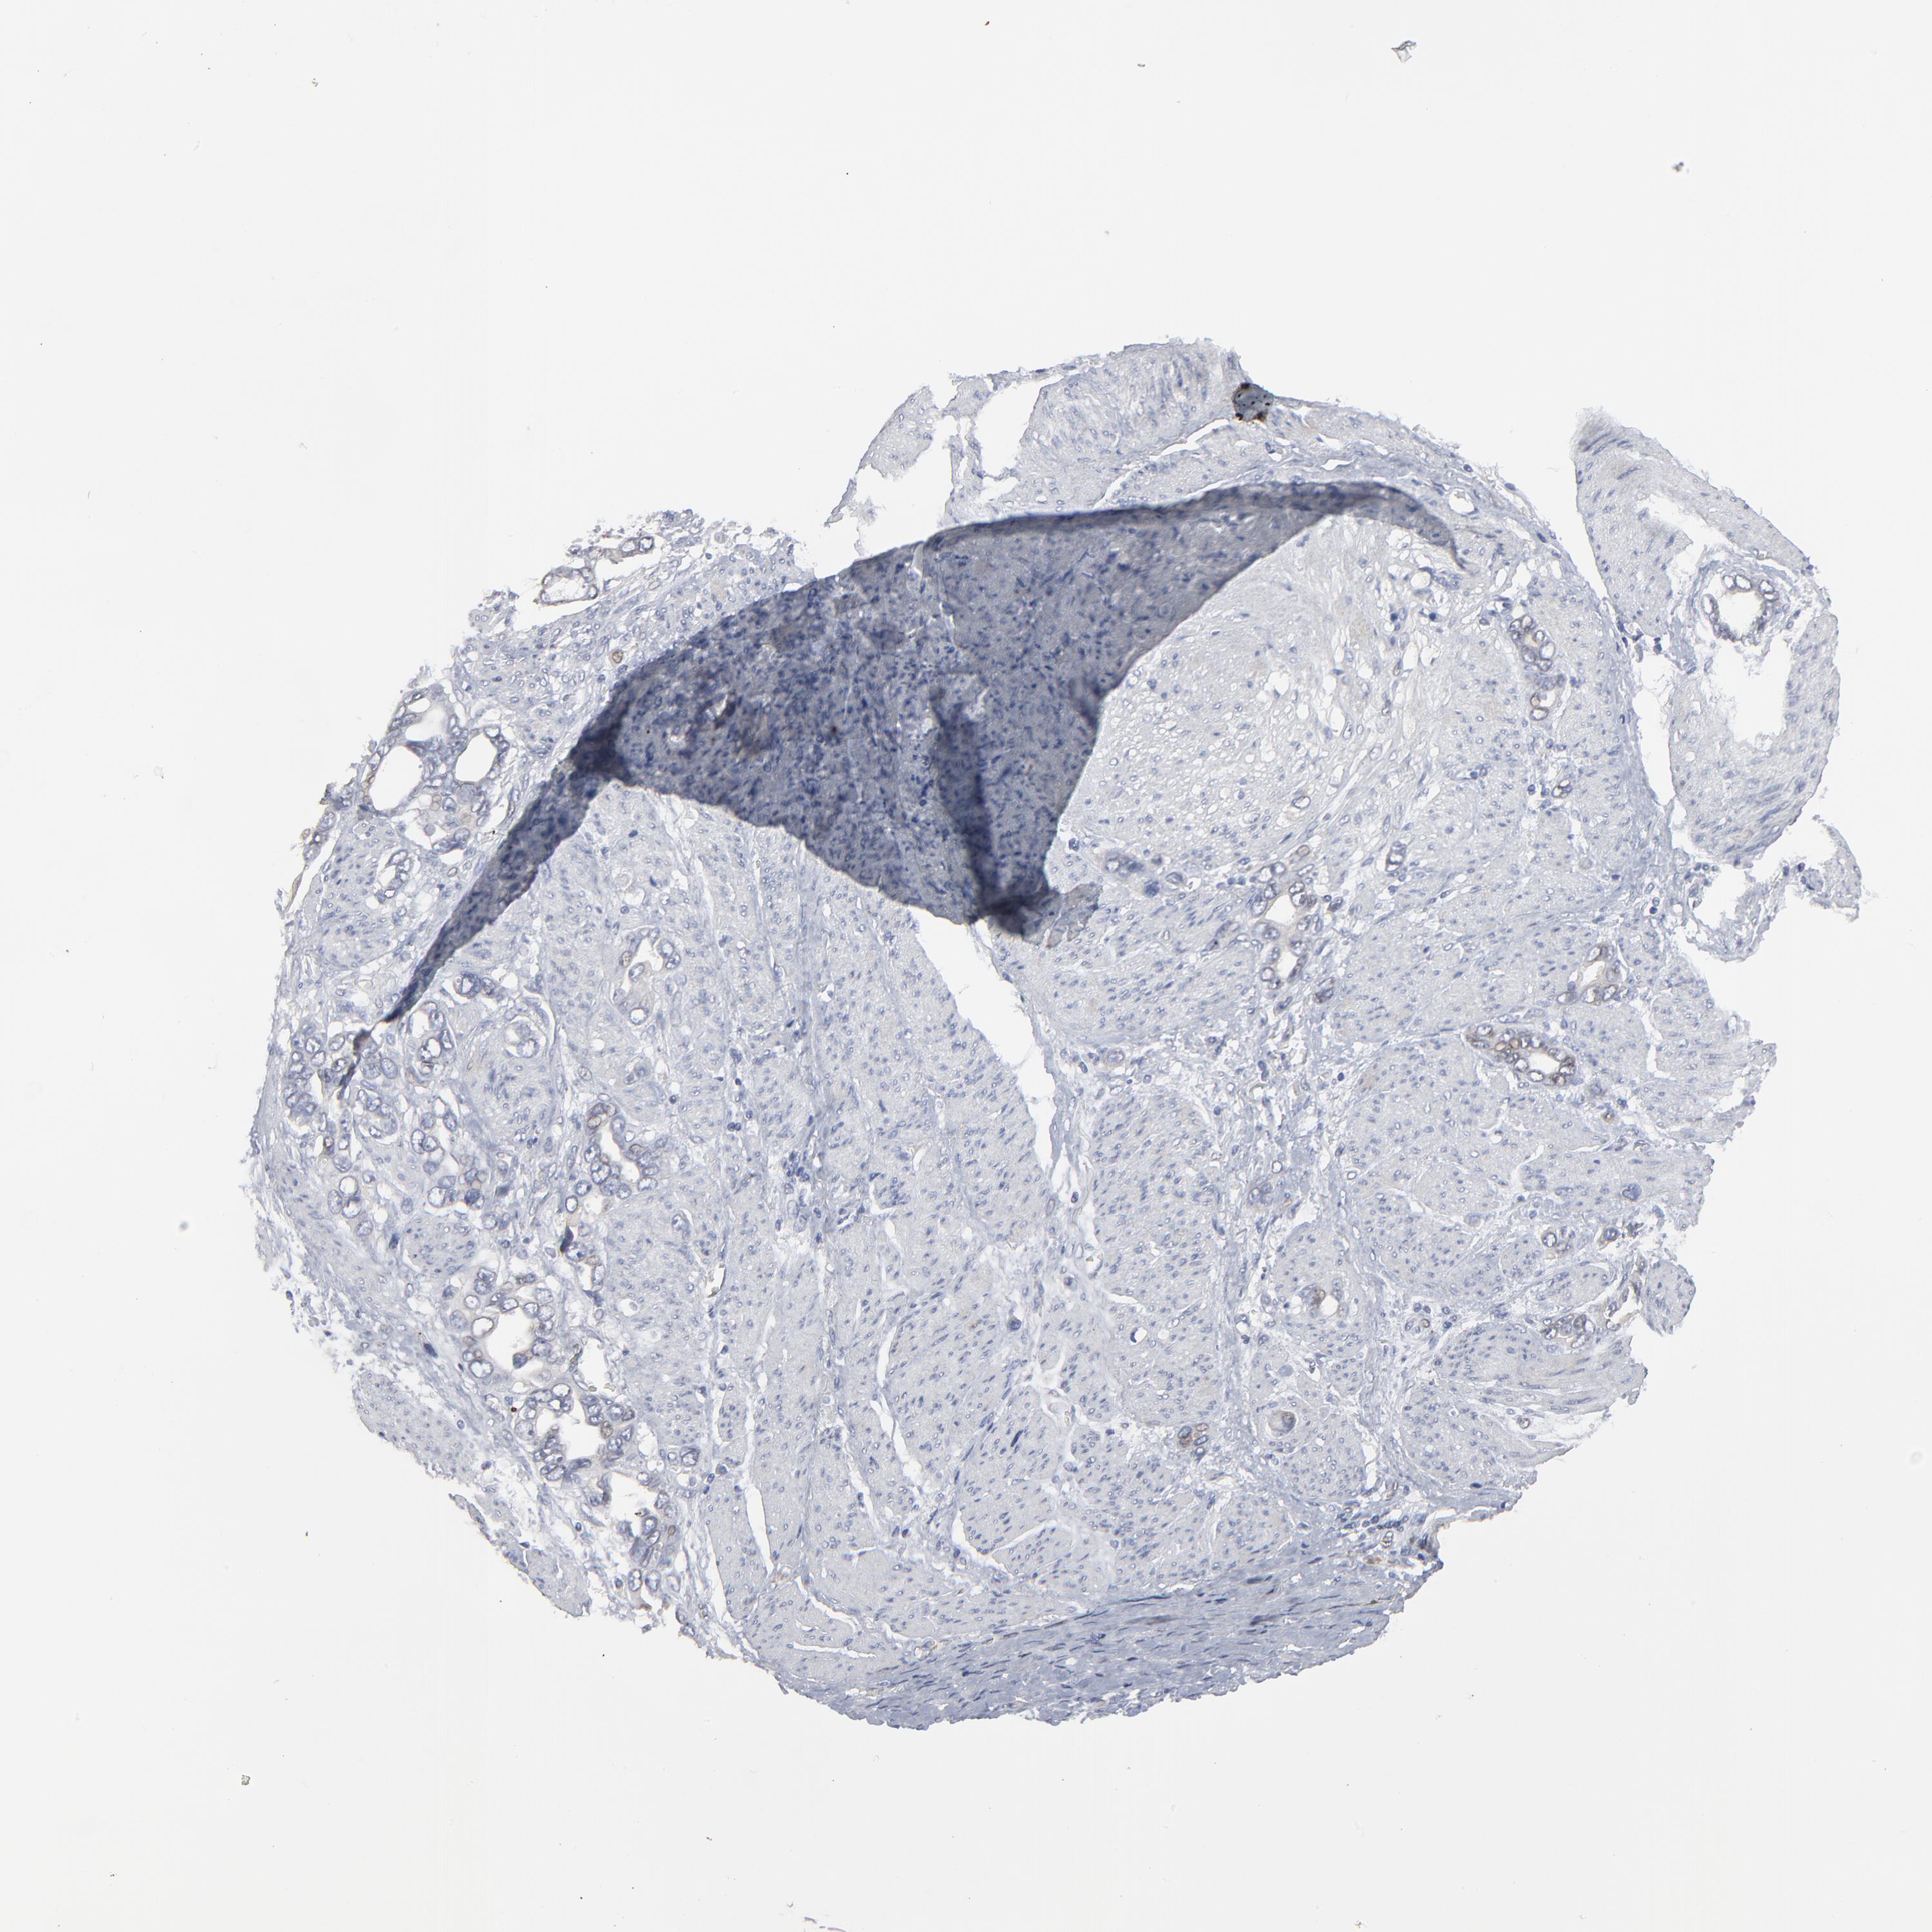

STOMACH CANCER - Protein expressioni

A mouse-over function shows sample information and annotation data. Click on an image to view it in a full screen mode. Samples can be filtered based on level of antibody staining by selecting one or several of the following categories: high, medium, low and not detected. The assay and annotation is described here.

Note that samples used for immunohistochemistry by the Human Protein Atlas do not correspond to samples in the TCGA dataset.

Antibody stainingi

Antibody staining in the annotated cell types in the current human tissue is reported as not detected, low, medium, or high, based on conventional immunohistochemistry profiling in selected tissues. This score is based on the combination of the staining intensity and fraction of stained cells.

Each image is clickable and will lead to virtual microscopy that enables deeper exploration of all samples and also displays staining intensity scores, fraction scores and subcellular localization as well as patient and tissue information for each sample.

Antibody HPA003435

Antibody HPA050204

Staining

High

Medium

Low

Not detected

Intensity

Strong

Moderate

Weak

Negative

Quantity

>75%

75%-25%

<25%

None

Location

Nuclear

Cytoplasmic/membranous

Cytoplasmic/membranous,nuclear

Adenocarcinoma, NOS